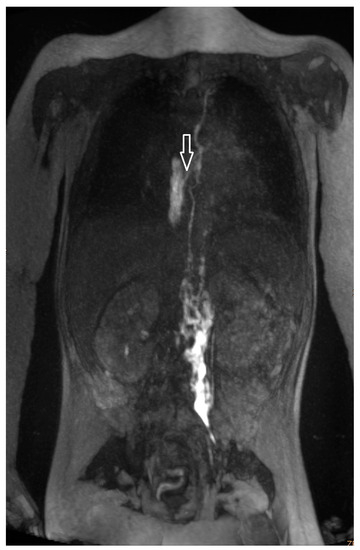

| 3 | 4 | increased signal neck, mediastinum, hilum, interstitial lung parenchyma, body wall edema, pleural effusion, ascites | abnormal, perfusion to the lung, intercostal flow, dermal backflow, | TV 6–9 bilateral into the lung | diuretics, sildenafil, MCT diet, non-invasive ventilatory support | no | persistent chylothorax, respiratory support |